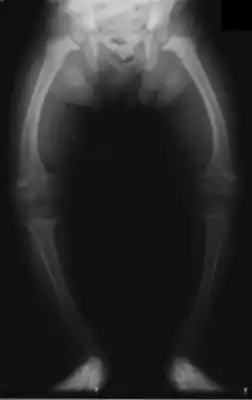

![]() Искривление нижних конечностей у 2-летнего ребёнка, страдающего рахитом *. | |

В период разгара прогрессируют изменения костной системы: остеомаляция грудной клетки, нижних конечностей, избыточный остеогенез (рахитические «чётки», «браслетки», лобные и теменные бугры черепа). Ребёнок может отставать в физическом и психическом развитии.

Возникшие при рахите деформации скелета остаются и во взрослом возрасте: нарушение осанки, изменения грудной клетки, костей нижних конечностей. У женщин перенесённый в детстве рахит может быть причиной сужения малого таза, что может затруднить течение родов и потребовать проведение кесарева сечения.